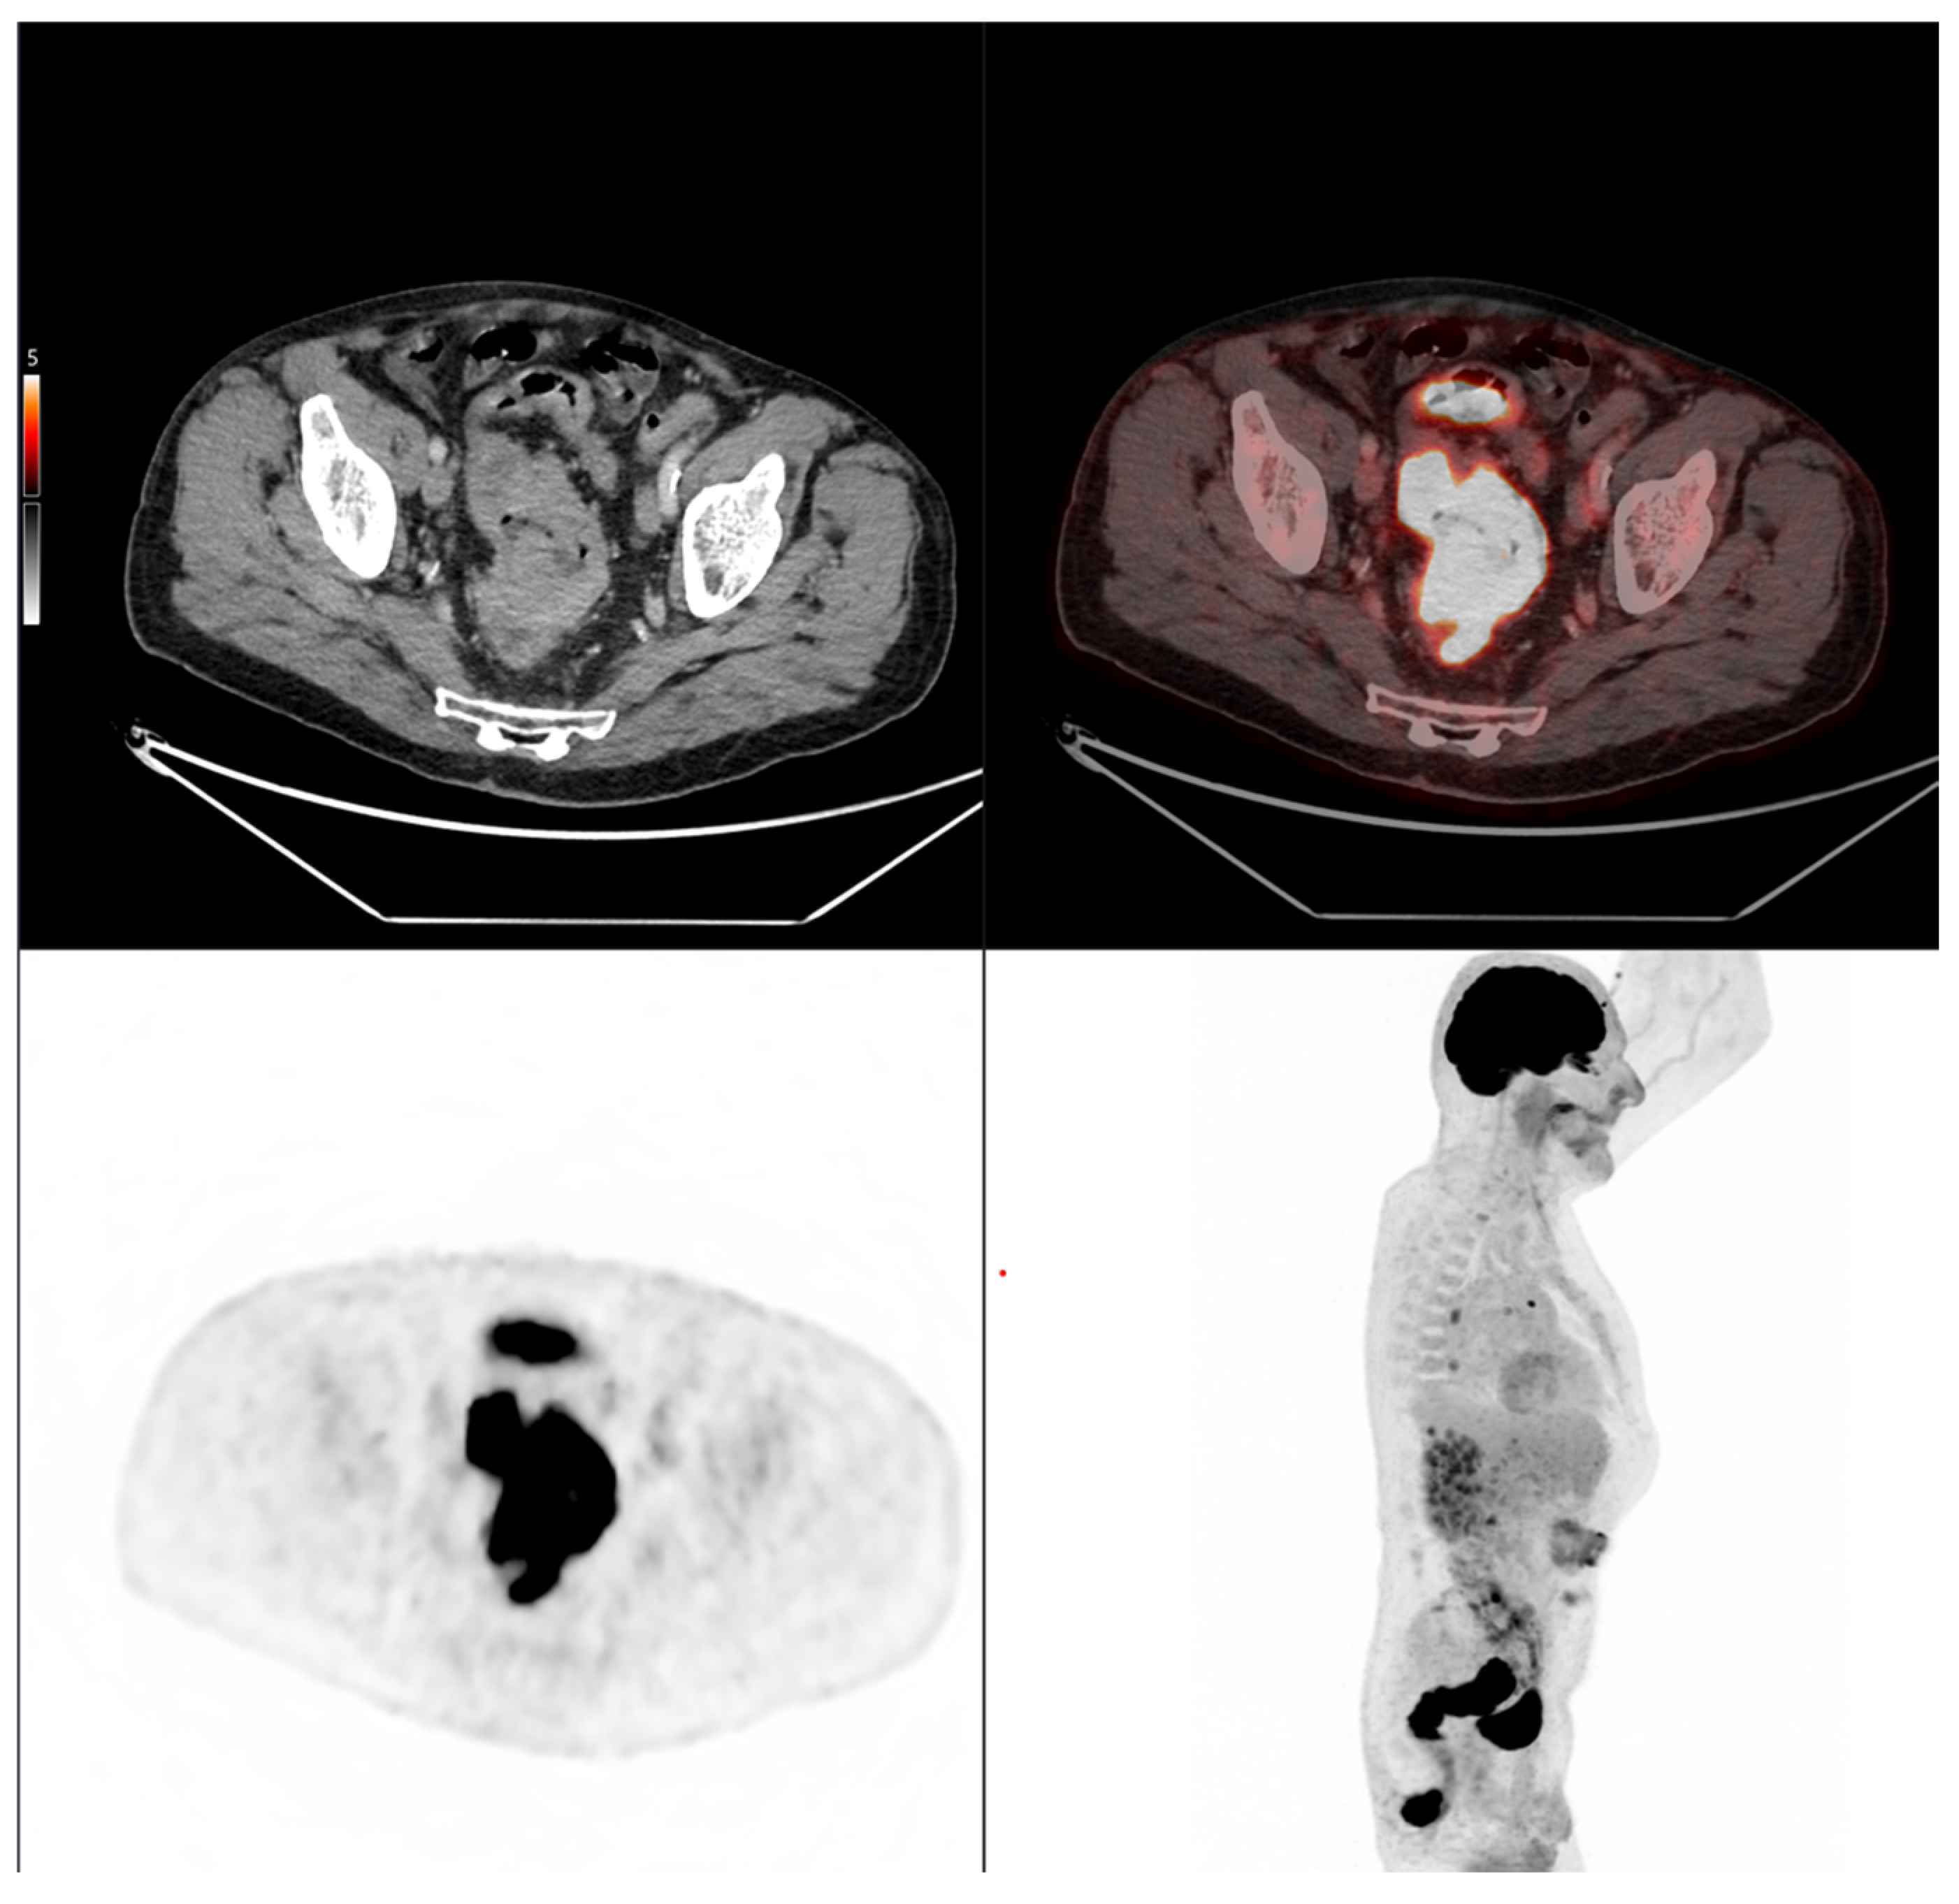

Altogether, these analyses demonstrate that MTV of the primary tumor is a consistent predictor of both OS and PFS. While OS was primarily influenced by sex and MTV, PFS was more strongly determined by UICC stage and MTV, as displayed in Figure 6. For a clearer understanding of the presented results, Figure 7 shows a representative example of manual delineation of the primary tumor on baseline FDG PET/CT.

Figure 7.

Representative example of manual delineation of a primary rectal tumor on baseline FDG PET/CT showing manual delineation of the metabolically active tumor volume (first row) on the PET image with corresponding fused PET/CT image and CT image with iodinated contrast medium (second row). Morphological features, including tumor shape (circular or semi-circular), cranio-caudal extension (in cm), and overall tumor volume (in cm3), were assessed on the CT image (often with contrast medium) coregistered with the PET images. Tumor shape was determined on the axial plane, cranio-caudal extension on the sagittal plane, and tumor volume after careful delineation on all planes. Iodinated contrast medium was administrated in 70% of cases after exclusion of contraindications. Metabolic parameters, including SUVmax, SUVmean, MTV and TLG, were systematically extracted from the segmented tumor (yellow in this figure). SUVmax (M in this figure) and TLG were automatically displayed. SUVmean could be obtained by simply replacing SUVmax with SUVmean in the parameter selection. MTV was automatically calculated from TLG and SUVmean values displayed on the workstation. The highlighted region in yellow represents the 3D contour of the primary tumor, excluding physiological uptake and non-tumor regions.

Case 1: An 80-year-old patient with stage IVA rectal cancer and synchronous anal carcinoma, presenting with a large circumferential primary tumor showing a craniocaudal extension well above the predictive cut-off (13.0 cm vs. 6.2 cm; volume: 79.2 mL) and a metabolic tumor volume markedly exceeding both prognostic thresholds (MTV 79.0 vs. 35.49 for OS and 32.08 for PFS). Baseline FDG PET/CT demonstrates locoregional nodal involvement and a solitary liver metastasis in segment VII. The patient experienced rapid disease progression, with a progression-free survival of 8 months and an overall survival of 27 months.